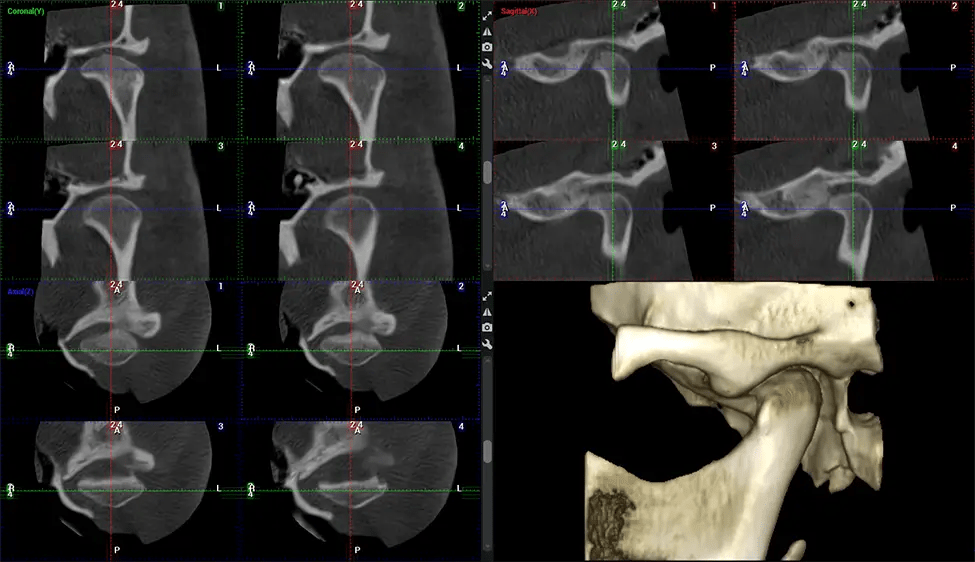

This 3D scan, called cone beam computed tomography, gives your dentist a more complete image of your oral anatomy and disease processes than a traditional X-ray. Unlike conventional X-rays, which capture a 2D image of your mouth from various angles, a 3D scan takes multiple digital X-rays for one image. It provides a complete view of your jaw, teeth, nerves, and soft tissues. This enhanced view allows dentists to detect minor issues not visible in traditional 2D scans, such as impacted wisdom teeth or bone fractures in the sinus cavity.

Another significant benefit is that 3D imaging provides more precise images of your bone structure. These images are more detailed, providing you with a more accurate diagnosis. An accurate diagnosis means better treatment for you.

When paired with extractions, dental implant placement, or bone grafting, CBCT technology can provide you with a quicker and much more comfortable experience. This is because the 3D image provides a more detailed picture of your entire oral cavity, allowing your dentist to walk you through each step of the process before it occurs. This often helps patients feel more prepared and comfortable overall, especially if they have had a traumatic experience with past dental treatments.

Planmeca Viso G7 CBCT ( Cone Beam CT Scan ) is designed to surpass the demands of industry leaders, specialists, and large institutions. It’s has a large ø25×30 cm sensor with four built-in cameras. It can capture unlimited volume sizes from a ø3×3 cm to a ø30x30cm volume capturing the skullcap through C7 on the cervical spine. The Planmeca Viso G7 offers the industry’s largest single volume scan of ø30×19 cm. It’s poised to handle advanced imaging modalities such as Planmeca ProFace® and Planmeca 4D™ Jaw Motion technology. The occipital head support allows an unimpeded view of facial tissue.

Our patented SCARA technology enables doctors to capture True Extraoral Bitewings that are as accurate at detecting caries as a 2D bitewing series, but with half the radiation dose. With our bitewings, doctors can view the apices of teeth on both jaws providing a more comprehensive view of the patients’ anatomy.